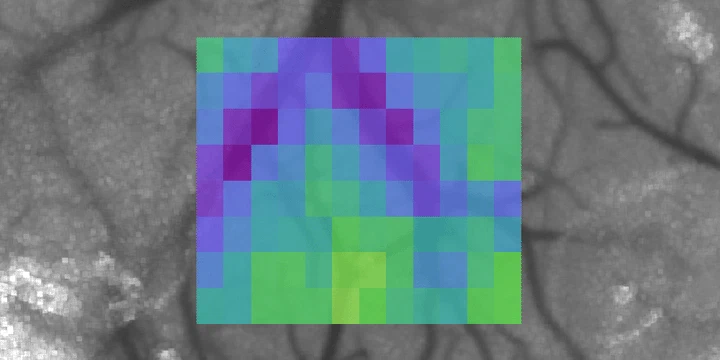

Vascular oxygen tension map (Sullender, 2018)We use oxygen-sensitive porphyrin probes for noninvasive, highly-sensitive optical oxygenation measurements based on phosphorescence quenching. While an injection of the dye is required, absolute oxygen tension ($p_{\ce{O2}}$) can be directly calculated from the lifetime ($\tau$) of the measured phosphorescence using the Stern-Volmer relationship:

In order to localize the phosphorescent signal, we use either two-photon excitation or structured illumination with a digital micromirror device (DMD). The latter is combined with laser speckle contrast imaging for multimodal imaging of cortical hemodynamics (cerebral blood flow + $p_{\ce{O2}}$). These systems are used to study both the acute and chronic dynamics of ischemic stroke.